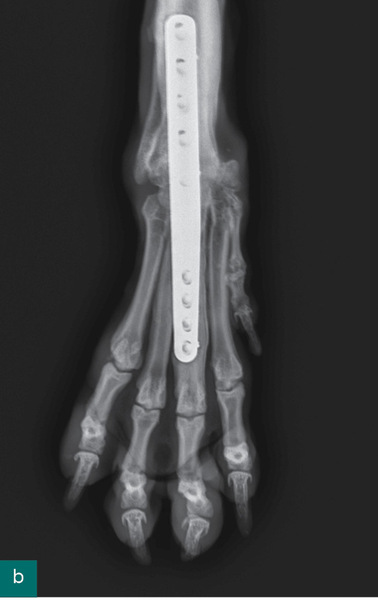

Ryc. 5. Stan zrostu kości trzy miesiące od wykonanego zabiegu artrodezy stawu nadgarstka.

W opisywanym przypadku zdecydowano o artrodezie wszystkich stawów nadgarstka (pankarpalnej), która jest wskazana, gdy zmiany dotyczą stawu przedramienno-nadgarstkowego, stawu śródnadgarstkowego lub nadgarstkowo-śródręcznego, gdy następuje uszkodzenie więzadeł dodatkowych nadgarstka, chrząstki włóknistej dłoniowej i więzadeł dłoniowych. Jeżeli staw przedramienno-nadgarstkowy nie jest uszkodzony, a zmiany dotyczą pozostałych struktur, bez przemieszczenia kości dodatkowej nadgarstka lub kości łokciowej nadgarstka, wystarczająca może być częściowa artrodeza nadgarstka (6, 7). Opisano trzy techniki całkowitej artrodezy nadgarstka: dłoniową, grzbietową, przyśrodkową. Idealny kąt dla pankarpalnej artrodezy to 10-12 stopni przeprostu. Podczas usuwania chrząstki stawowej należy zwrócić uwagę, aby usunąć ją do poziomu kości podchrzęstnej, nie pozostawiając dużych szczelin między powierzchniami stawowymi. Umieszczając przeszczepianą tkankę kostną między powierzchniami stawowymi, należy zachować jak najkrótszy czas odsłonięcia materiału przeszczepianego (3, 8). Ważne jest, aby jedna ze śrub znajdowała się centralnie w kości promieniowej nadgarstka. Można użyć igieł iniekcyjnych, aby umieścić płytę precyzyjnie, w odpowiednim miejscu.

Opisane powikłania przy zabiegu artrodezy obejmują poluzowanie śrub, złamanie zrostu kostnego, zakażenie, złamanie kości śródręcza, niepełną artrodezę i ciągłe zaburzenia chodu. Aby zmniejszyć ryzyko powikłań, należy zwracać uwagę, by nie uszkodzić ważnych anatomicznie struktur, usunąć całą chrząstkę ze wszystkich powierzchni, w odpowiedni sposób dogiąć płytę, tak aby nie było zbyt dużego, ale też zbyt małego kąta przeprostu. Trzeba również uważnie dobrać rozmiar płyty, by obejmowała ponad 50% długości kości śródręcza III (9). Wkręty należy umieszczać tak, aby śruby w kości śródręcza nie przekraczały 40% średnicy kości (10).

Ważne są też zalecenia pooperacyjne, między innymi ograniczenie ruchu, antybiotykoterapia, regularne zmiany opatrunku, zabezpieczenie rany przed wylizaniem poprzez używanie kołnierza. W jednej publikacji badano na grupie 17 psów czas gojenia się bez powikłań artrodezy pankarpalnej (12). U wszystkich pacjentów położono płytę dogrzbietowo oraz po zabiegu założono opatrunek gipsowy na sześć tygodni, a następnie opatrunek Roberta Jonesa na osiem tygodni, przy czym przez cały czas ograniczano ruch. W stawach międzynadgarstkowym i nadgarstkowo-śródręcznym zrost kostny nastąpił między 9. a 12. tygodniem, a w stawie promieniowo-nadgarstkowym między 17. a 30. tygodniem po operacji. Autorzy badania doszli do wniosku, że ocenę radiograficzną należy wykonać po sześciu i 12 tygodniach od zabiegu (12).